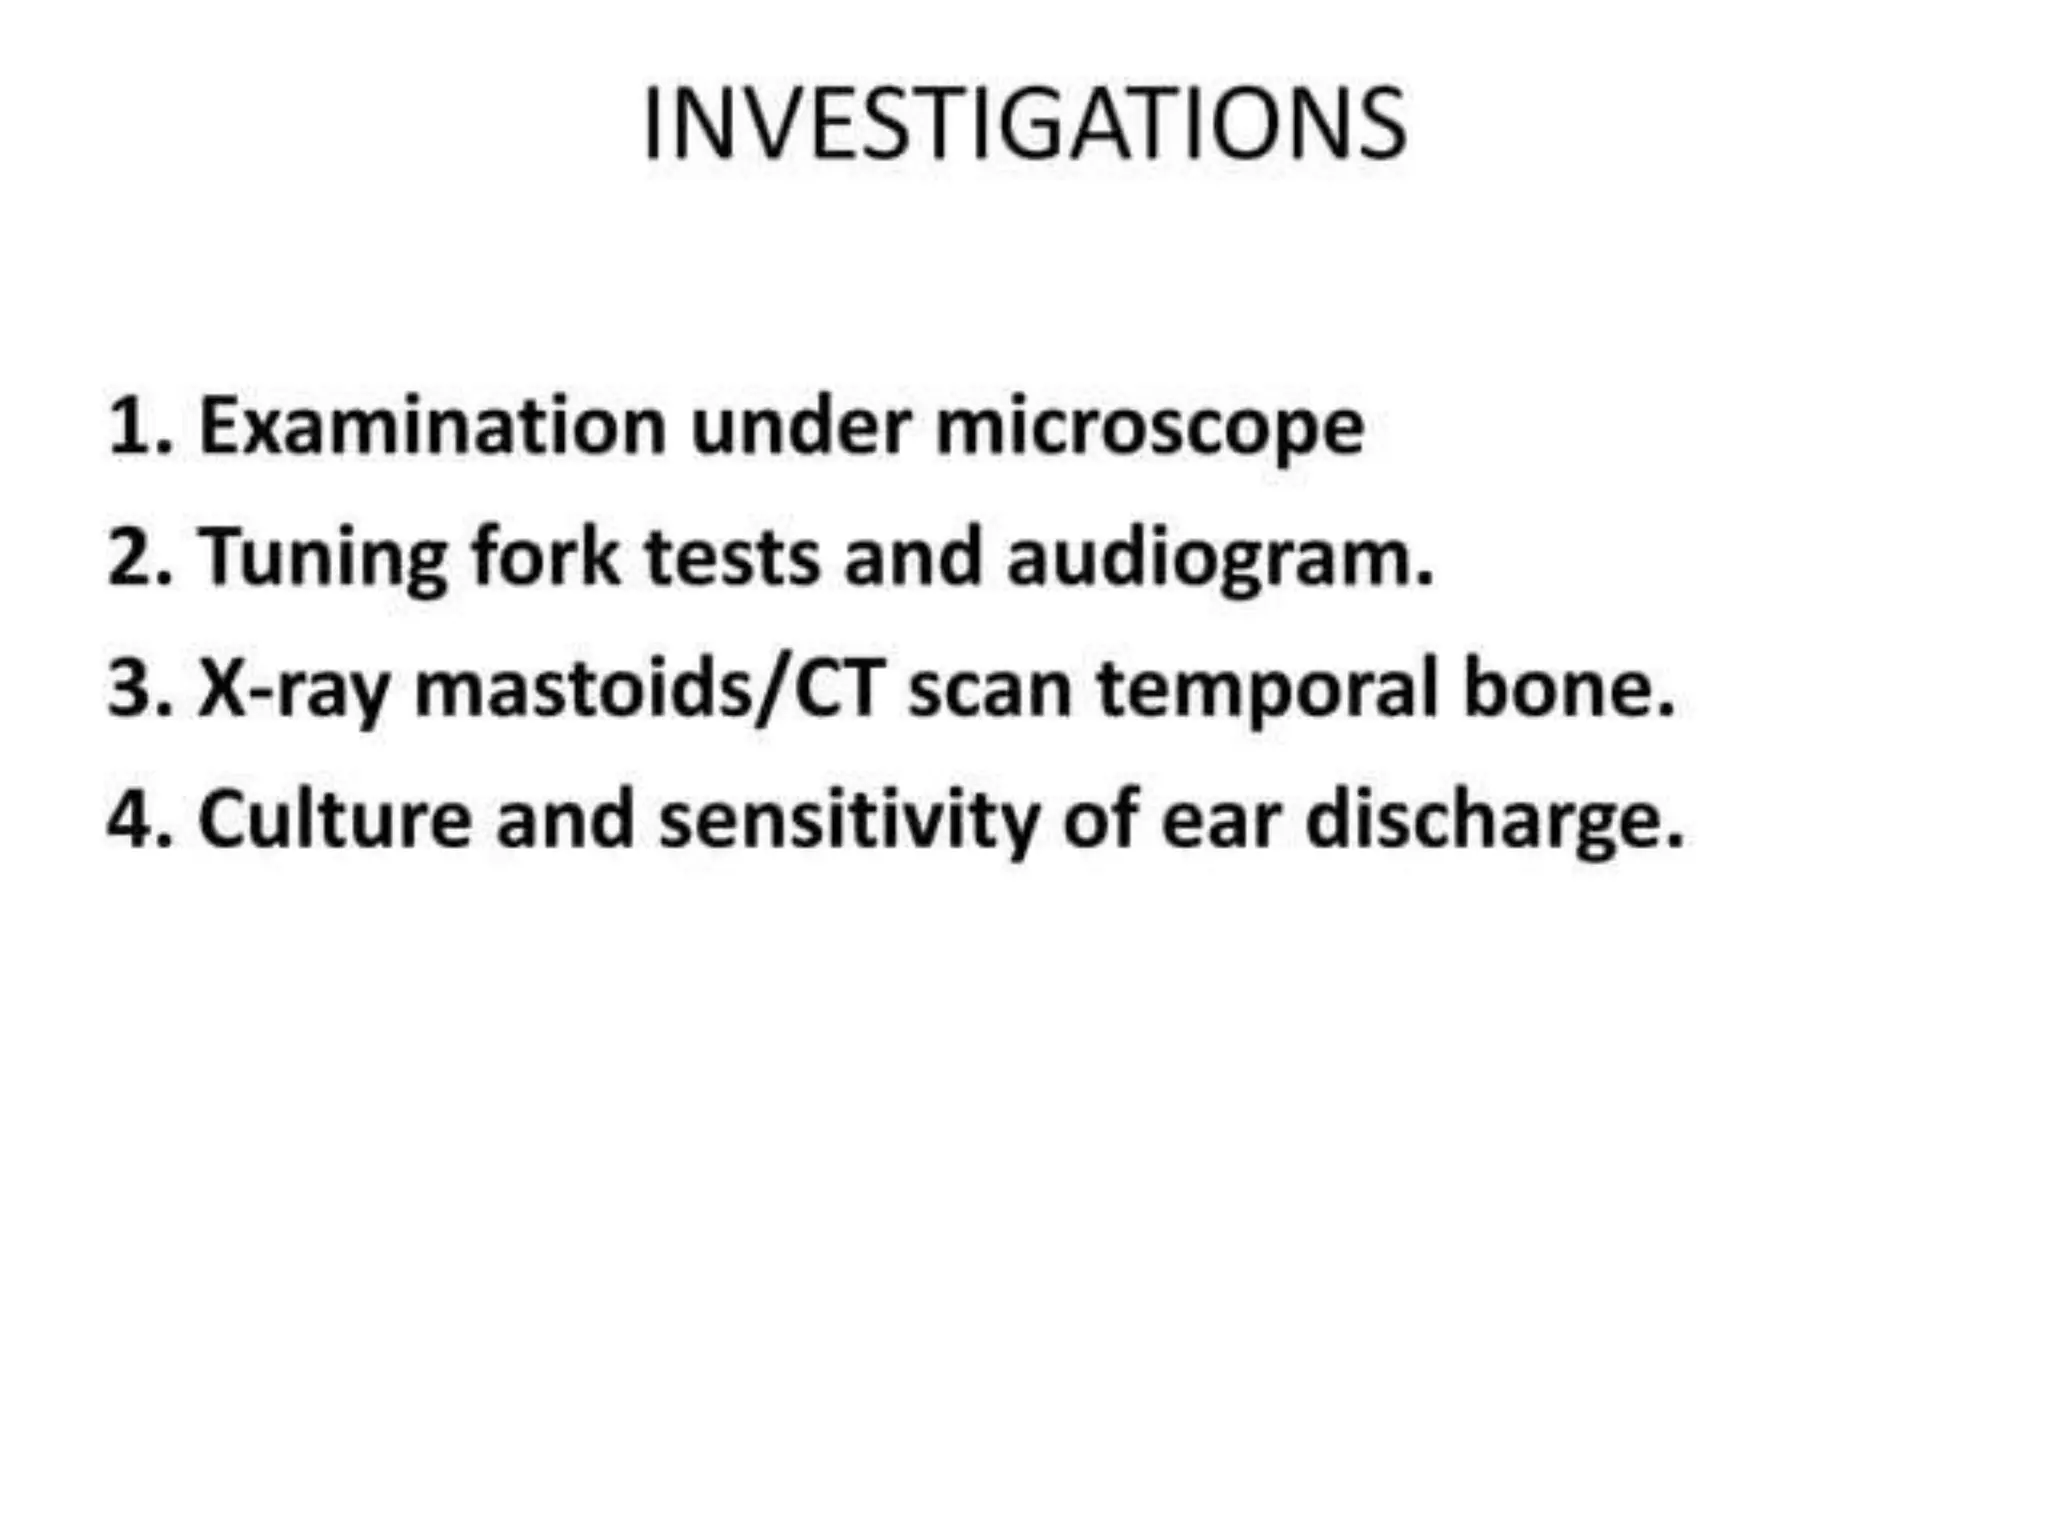

Chronic otitis media is a chronic inflammation of the middle ear and mastoid cavity that presents with recurrent ear discharge through a perforated eardrum. It has several subtypes depending on the state of the eardrum perforation and epithelium. It can be caused by prior acute otitis media, genetics, environment, eustachian tube issues, gastroesophageal reflux disease, craniofacial abnormalities, or immune deficiency.